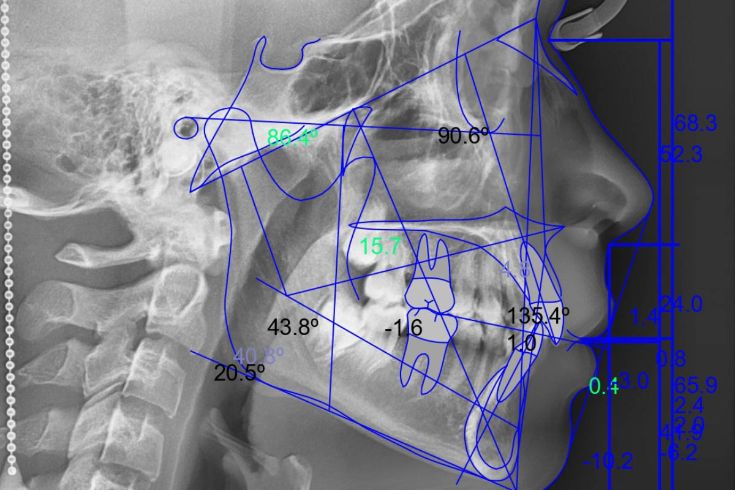

Permite medir y analizar las estructuras óseas del cráneo, cara y mandíbula (Ricketts, Jarabak, Roth, etc.). Esencial en ortodoncia y cirugía maxilofacial para definir planes de tratamiento.